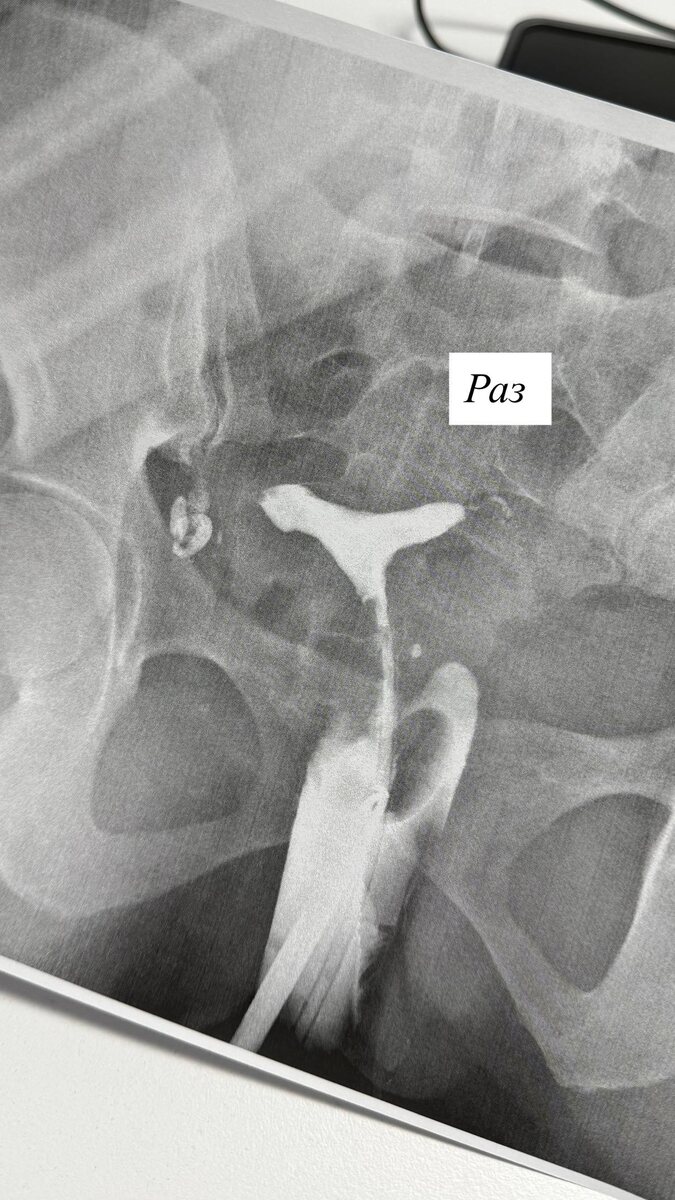

Молодая девушка 28 лет , в анамнезе - две операции по поводу кист яичников , сейчас признаки спаечного процесса в брюшной полости и безуспешные попытки к 🤰

Посмотрели сегодня проходимость маточных труб . Слева - не проходимо , спайки все замуровали. Слева - на серии первых снимков - глухо, потом я максимально «перекрестом» зафиксировала пулевыми щипцами цервикальный канал и под давлением ввела контрастное вещество. И ура - слева « восстановили» проходимость ! Выход контрастного вещества в малый таз 💫🔥 а значит маточная труба проходима !

Сейчас план - планирование беременности в естественном цикле , будем ловить овуляцию слева ☘️